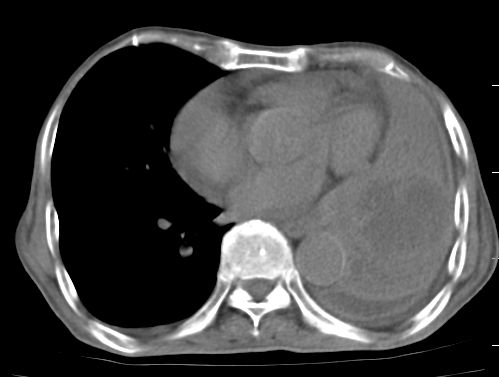

标题: CT10141:男、84岁,咳嗽、咯血1年。 [打印本页]

标题: CT10141:男、84岁,咳嗽、咯血1年。

支持左侧中央型肺癌伴下叶肺不张\\纵隔淋巴结转移.左侧包裹性胸腔积液\\心包积液.左侧少量胸腔积液..慢性支气管炎伴部分间质纤维化.

咯血病史较长,左肺下叶实变,体积未明显缩小,隐约可见血管影及坏死阴影,双肺门及纵隔淋巴结增大,心包增厚积液,纵隔右移位,单侧胸腔积液,首先考虑:大叶型肺泡癌伴纵隔心包转移。